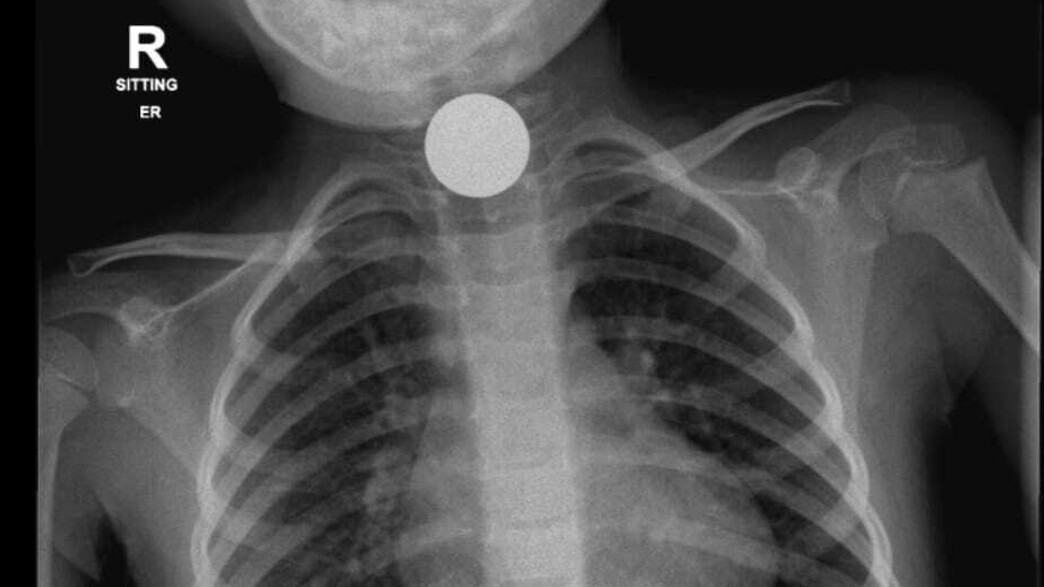

בעוד ב-2 מתוך המקרים לא היה צורך בהתערבות ניתוחית, ולאחר טיפול מתאים העצמים הזרים יצאו באופן טבעי והילדים שוחררו לביתם, במקרה השלישי והרביעי המציאות הייתה שונה; במקרה השלישי מדובר על ילדה בת 7 שבוצע לה צילום רנטגן בו נראו חלקי משחק מגנט שהתמקמו במעיים, וגם לאחר 72 שעות לא חלה כל התקדמות או שינוי במקום הימצאם. במקרה הרביעי מדובר על פעוטה בת 4 שבצילום הרנטגן נראו מטבעות כסף נמצאות בוושט עם דחיקה של הקנה, דבר שמנע ממנה לנשום כראוי.

הניתוח של בת ה-4 התקיים אמש בשעות אחר הצוהריים בהובלתם של ד"ר עופר גליק וד"ר ירדן טננבאום ממחלקת אא"ג/ניתוחי ראש צוואר. הניתוח של בת ה-7 התקיים הבוקר בהובלתה של ד"ר חני טאף. לשמחת כולם, הניתוחים הסתיימו בהצלחה - מטבעות הכסף וחלקי המשחק הוצאו בשלמותם והילדות הועברו להמשך טיפול והשגחה במחלקת הילדים של ביה"ח הציבורי אסותא אשדוד.